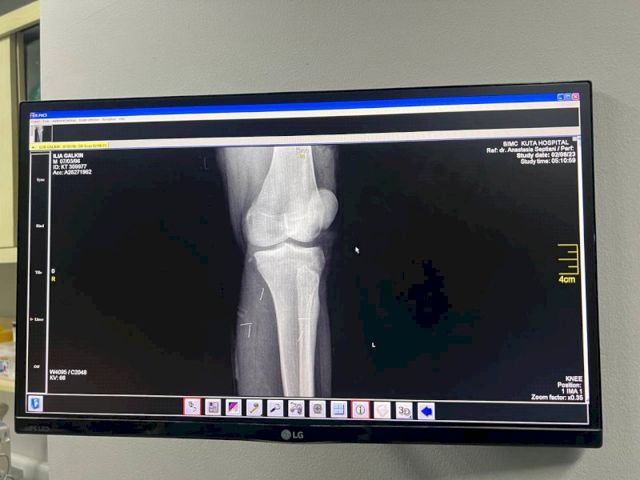

По его словам, сразу после аварии друзья ведущего повезли его в частную больницу. Однако цены там были «сумасшедшие». Тогда Илью отвезли в госпиталь BIMC Kuta. На первичном осмотре выяснилось, что у него множественные переломы и открытый перелом бедренной кости, разорваны мышцы и связки, требуются серьезные операции.

«Первую операцию сделали сегодня, он сейчас в реанимации. Говорят, что состояние стабильное. Операция и нахождение в больнице стоят около 30-50 тыс. долларов. Для нашей семьи это большие деньги, поэтому друзья открыли сбор на лечение. Но волнует и вопрос реабилитации. Либо Илья будет проходить ее там, а это очень дорого, либо его как-то надо транспортировать в Россию», - говорит Павел Галкин.